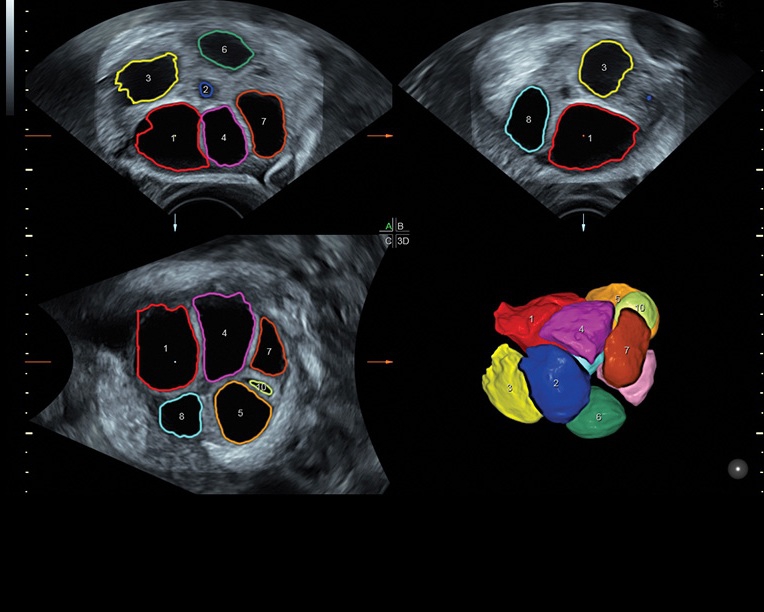

Ультразвуковая платформа Voluson S8 представляет собой оборудование экспертного класса с передовыми возможностями и высоким уровнем автоматизации процессов. Она позволяет проводить сканирование в режимах 2D, 3D и 4D с высоким качеством изображений.

Аппарат Voluson S8 базируется на надежной платформе VCA, которая имеет множество положительных отзывов. Она обладает высококонтрастной технологией объемной реконструкции, обеспечивая качественное воспроизведение изображений. Информация выводится на широкоформатный цветной монитор размером 23 дюйма для убедительной демонстрации плода будущим родителям и облегчения работы врача.

Система предназначена как для коммерческой, так и для государственной медицины, в клиниках с высокой загруженностью пациентами. Voluson S8 отлично справляется с большим объемом работы благодаря шаблонизированным отчетам и автоматизации обработки и постановки диагнозов с помощью функций SonoNT, SonoVCAD, SonoAVC и STIC. Это делает аппарат коммерчески выгодным и окупаемым в ближайшей перспективе.

• Сложные инструменты для оценки качества плода: Сканер оснащен инновационными инструментами, позволяющими проводить детальную оценку состояния плода, включая его сердечную деятельность, анатомию и кровоток.

Технологии, доступные на ультразвуковом сканере Voluson S8:

• Технология SonoRenderlive: Эта технология облегчает получение 3D/4D изображений путем автоматического изменения положения плоскости визуализации в зависимости от движений плода. Она позволяет получить реалистичные и объемные изображения, что полезно для демонстрации плода будущим родителям и для дополнительного анализа.